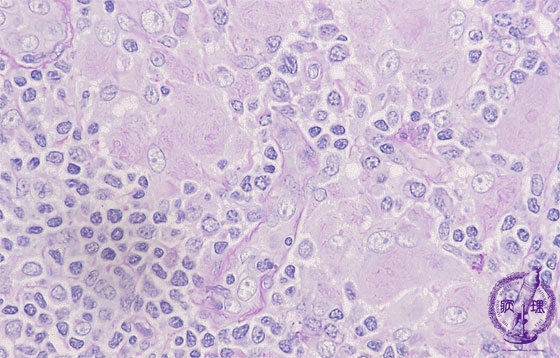

Microscopic view, (PAS staining); The cytoplasm are packed with rod shaped inclusions bound by a single membrane. The inclusions are positive for PAS reaction